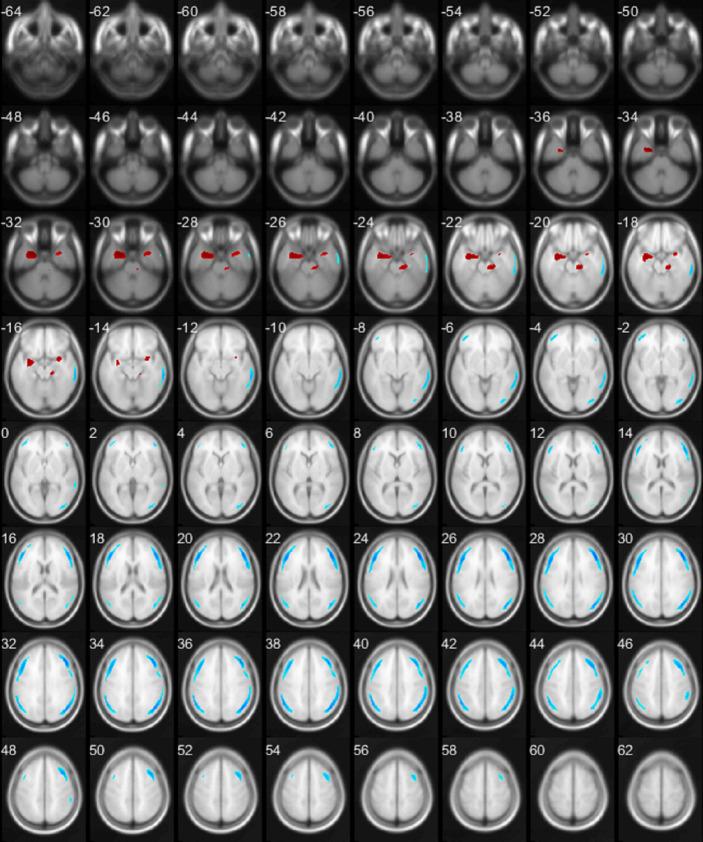

In the current study, Statistic Parameter Mapping (SPM) demonstrated that the major depression patient group (n = 38) had significant regional metabolic differences (clusters of continuous voxels) as compared to the non-major depression group (n = 96) with the criteria of height threshold T = 4.38 and extent threshold > 100 voxels. The five significant hypo- and three hyper-metabolic clusters from the computed T contrast maps were localized on the glass-brain view, consistent with published brain metabolic changes in major depression patients. Subsequently, using these clusters as features for classification learner, the fine tree and medium tree algorithms from 25 classification algorithms best fitted our data (accuracy 0.85%; AUC 0.88; sensitivity 79%; and specificity 88%).

在本研究中,统计参数映射(SPM)显示,与无重度抑郁症组(n=96)相比,重度抑郁症患者组(n=38)具有显著的区域代谢差异(连续体素簇),高度阈值 T=4.38 和扩展阈值>100 体素。从计算的 T 对比度图中获得的五个显著低代谢和三个高代谢簇在玻璃脑视图上定位,与重度抑郁症患者的大脑代谢变化一致。随后,使用这些簇作为分类学习者的特征,来自 25 种分类算法的精细树和中树算法最适合我们的数据(准确性 0.85%;AUC 0.88%;灵敏度 79%;特异性 88%)。